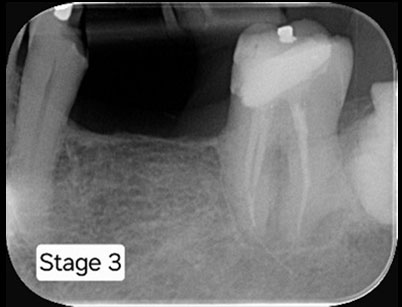

RCT completed with posts placed.

Follow up x-ray taken after 6 months.